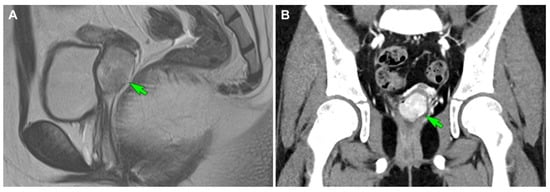

3.1. Case 1: Primary ASPS of the Uterine Corpus

3.1.1. Clinical Presentation

3.2.1. Clinical Presentation

3.2.2. Pathological Findings